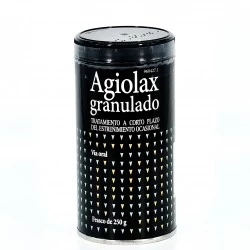

¿Sufres de estreñimiento? Encuentra alivio con Dulcolaxo Bisacodilo 5mg (30 comprimidos), Agiolax en 250g y Plantaben 3,5g (30 sobres). Estas pastillas, remedios y medicamentos libres de receta, son opciones efectivas para tratar el estreñimiento. ¡Prueba ahora!